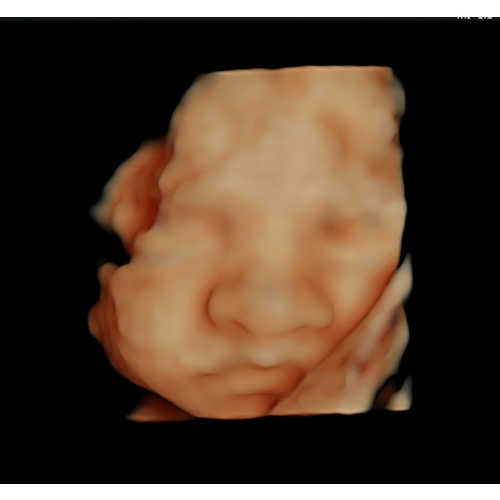

Dit is ons boze meisje🤣 Ik blijf heel erg lachen om deze foto! Deze is met 27+4 gemaakt maar omdat mevrouw met haar voet op haar hoofd lag en weigerde te draaien mag ik maandag terug komen! Hopelijk ligt ze dan goed en is ze dan minder chagerijnig😂😂